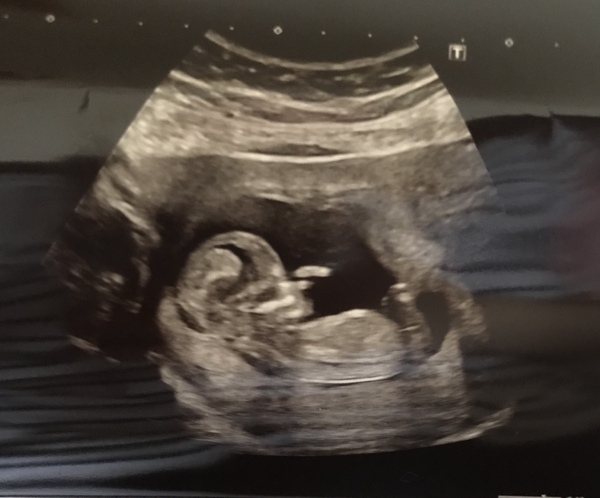

Trying to spot any hint of a nub here for fun... but really can’t see anything 😂